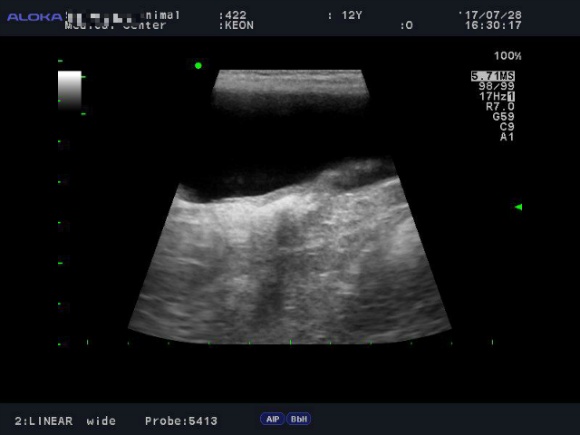

<7월28일> 다시 원점..도로아미타불입니다. 다시봐도 속상하네요 (근데 이게 담낭이 맞긴 한건가..급혼란..)

어제받은 초음파사진들은 몇장 안되니 그냥 다 올려볼게요

(이제와서 뭐가 뭔지도 몰라보는 이 모지란 반려인간..ㅜ)